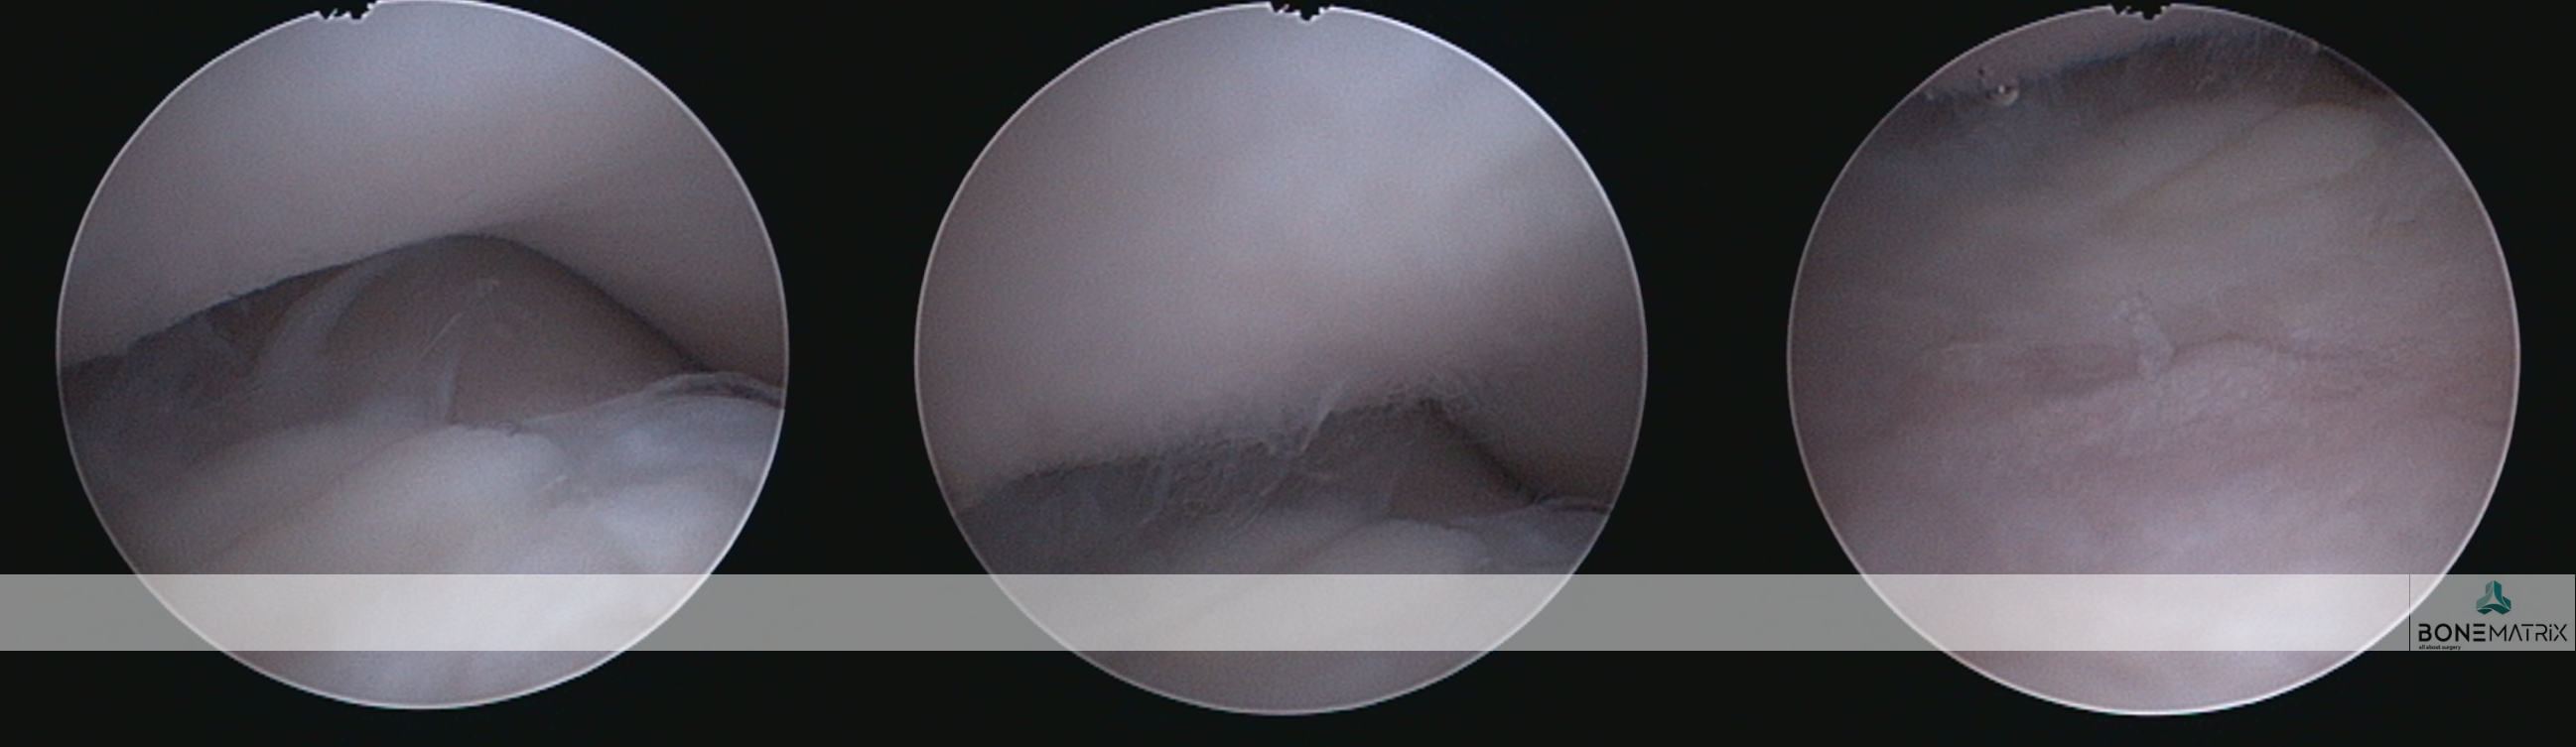

O que é?

A osteocondrite dissecante é uma condição que surge durante o crescimento devido a um distúrbio na diferenciação das células de cartilagem, o que resulta numa falha na ossificação endocondral (processo fundamental do desenvolvimento esquelético do feto e do cachorro em crescimento). Este defeito no crescimento resulta no aparecimento de um defeito ósseo tipicamente apresentado na cabeça do úmero, da qual se destaca um “flap” de cartilagem.

Como é feito o diagnóstico de OCD?

A suspeita surge quando se deteta claudicação, dor e desconforto no ombro, entre os 6 e 10 meses de idade. Alguns pacientes podem passar assintomáticos durante os primeiros anos, e mostrar desconforto numa fase mais avançada da doença e da idade. Após exame ortopédico, o diagnóstico é geralmente confirmado com um estudo radiográfico.

Situações mais subtis podem carecer de confirmação com estudo de TAC ou artrografia (radiografia com contraste articular).

Quais os tratamentos disponíveis para OCD do ombro?

A artroscopia é o tratamento “gold standard” da OCD. Neste procedimento minimamente invasivo, são efetuados pequenos orifícios (2.4mm) através dos quais são introduzidas uma câmara de filmar e instrumentos apropriados. O “flap” articular é removido desta forma, sem necessidade de recorrer a uma abertura cirúrgica da articulação. Este processo de tratamento garante uma recuperação rápida e confortável.

É utilizado Synacart em casos onde a lesão osteocondral é muito extensa e a simples remoção do “flap” pode revelar-se insuficiente. Nestes casos podemos optar por uma técnica de “ressurfacing” que tem como objetivo cobrir o defeito ósseo com um implante Synacart ou um implante especialmente desenhado para o efeito. Estes implantes têm uma porção metálica porosa que integra no osso subcondral e uma superfície de polímero polido que mimetiza a superfície de cartilagem perdida.